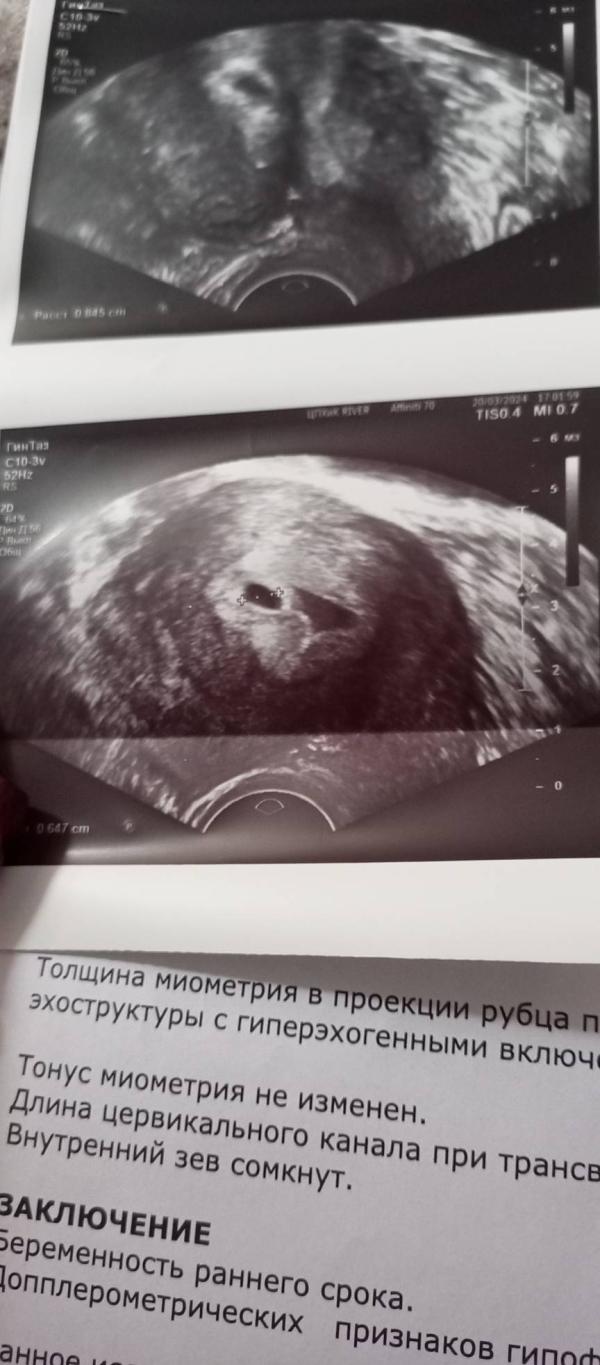

Мои подозрения о поздней овуляции подтвердились. ПЯ всего 6.5 мм, эмбриончика пока не видно, через 2 недели схожу, уже все должно быть.

И самое главное мой шов. 8 мм, сказали хороший шов, показаний для прерывания беременности нет.